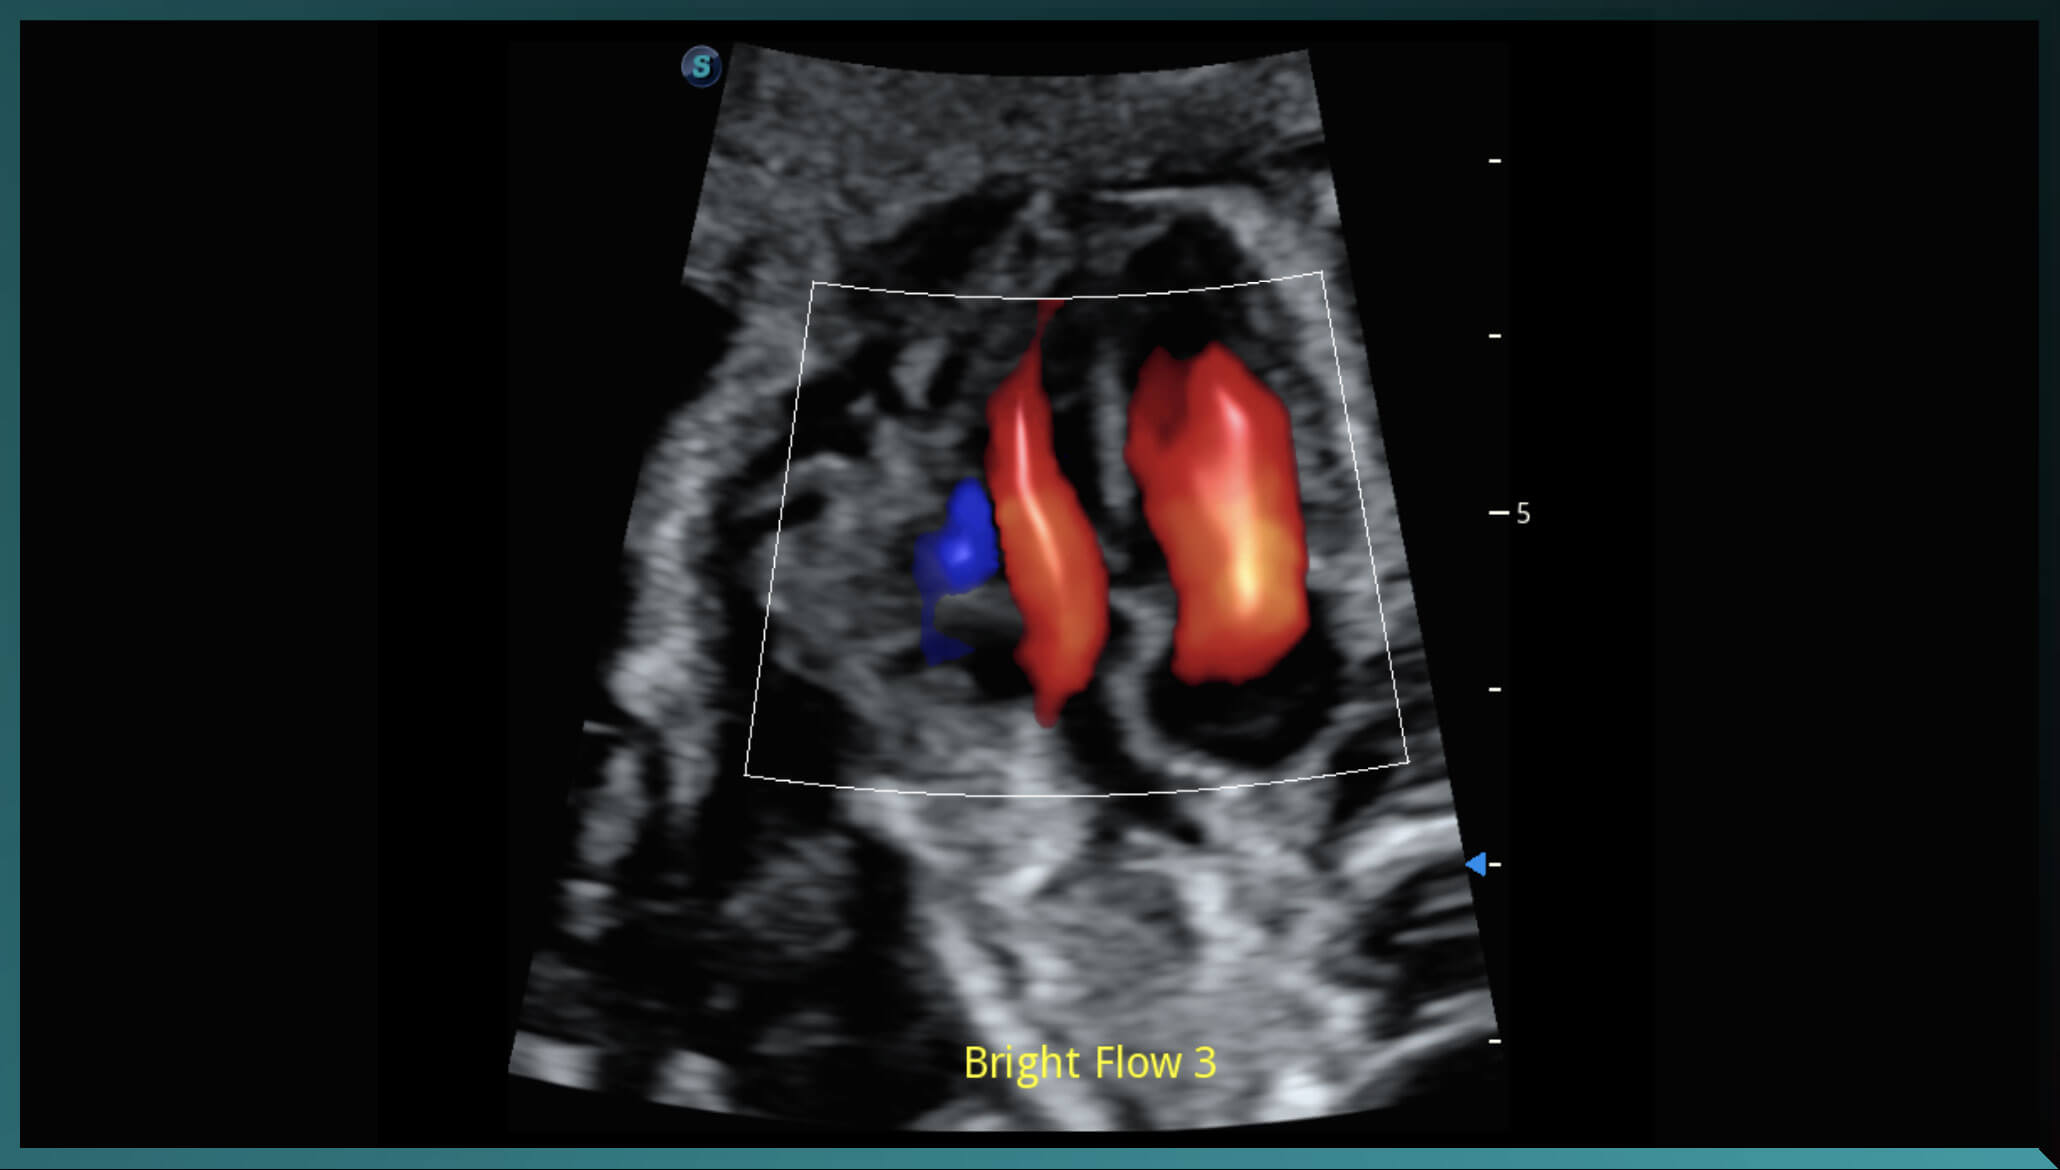

Bright Flow

Dòng chảy Doppler màu giống 3D giúp tăng cường khả năng xác định ranh giới của thành mạch mà không cần sử dụng đầu dò 3D. Đổi mới này giúp các bác sĩ hình dung trực quan hơn về lưu lượng dòng máu.